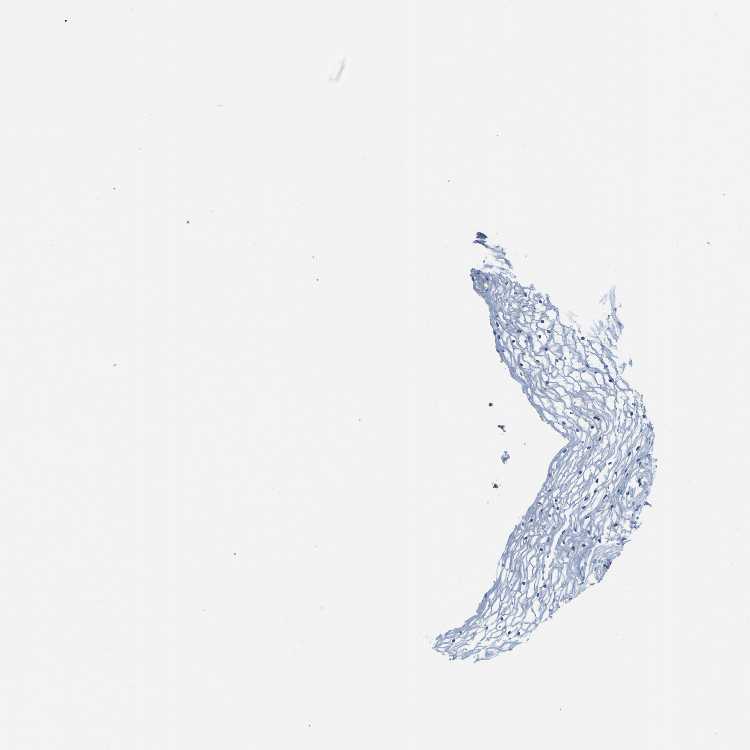

VAGINA - Antibody stainingi

Antibody staining in the annotated cell types in the current human tissue is reported as not detected, low, medium, or high, based on conventional immunohistochemistry profiling in selected tissues. This score is based on the combination of the staining intensity and fraction of stained cells.

Each image is clickable and will lead to virtual microscopy that enables deeper exploration of all samples and also displays staining intensity scores, fraction scores and subcellular localization as well as patient and tissue information for each sample.

Antibody HPA011088Antibody HPA012123Antibody CAB037128Antibody CAB037288

Squamous epithelial cells MediumMediumHighHigh